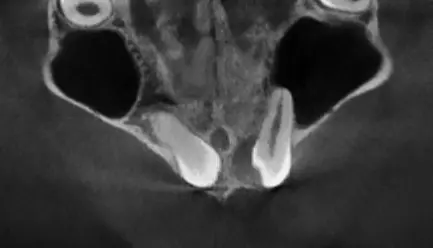

TOMOGRAFÍA PARA ENDODONCIA

Evaluación necesaria en campo reducido para visualizar los conductos radiculares o probables fracturas.